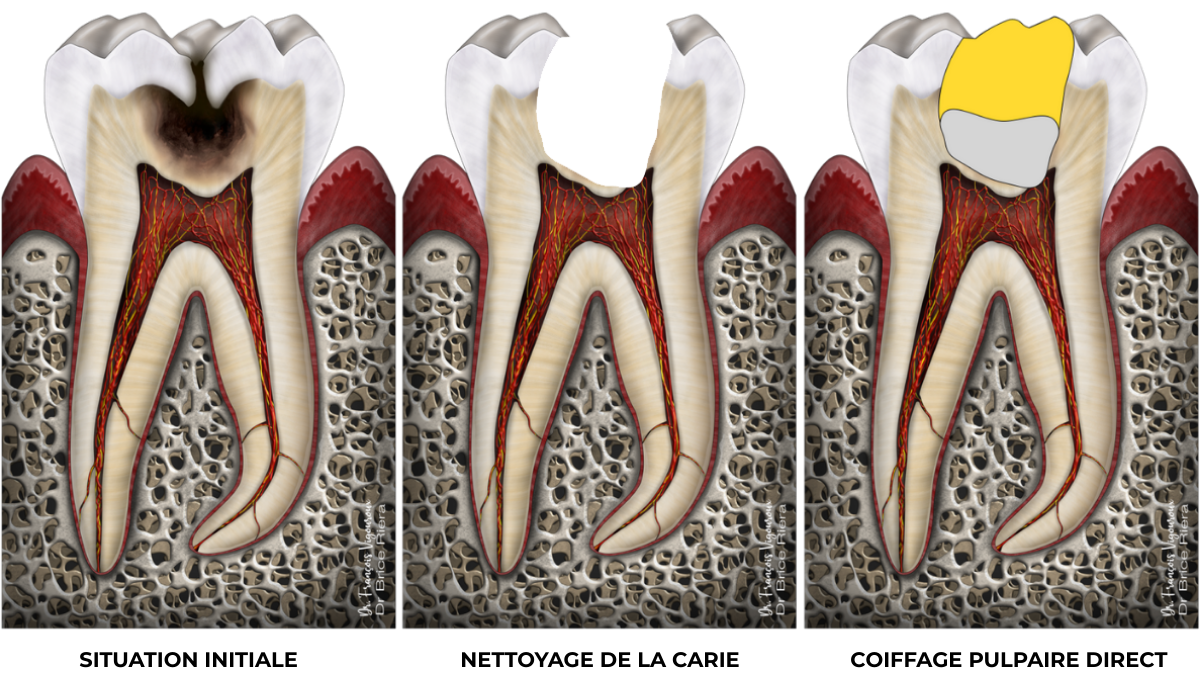

Pulpotomie partielle

Parfois il y a besoin d’aller volontairement un peu plus loin dans la pulpe. C’est le cas lorsque l’hémostase n’est pas obtenue, ou bien lorsqu’il y a la nécessité de réaliser un minimum de coffrage pour maintenir le biomatériau bioactif.

Cas clinique

Pulpotomie partielle : 88,2% de taux de succès